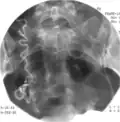

Эмболизация микрокатетером через яичниковую артерию.